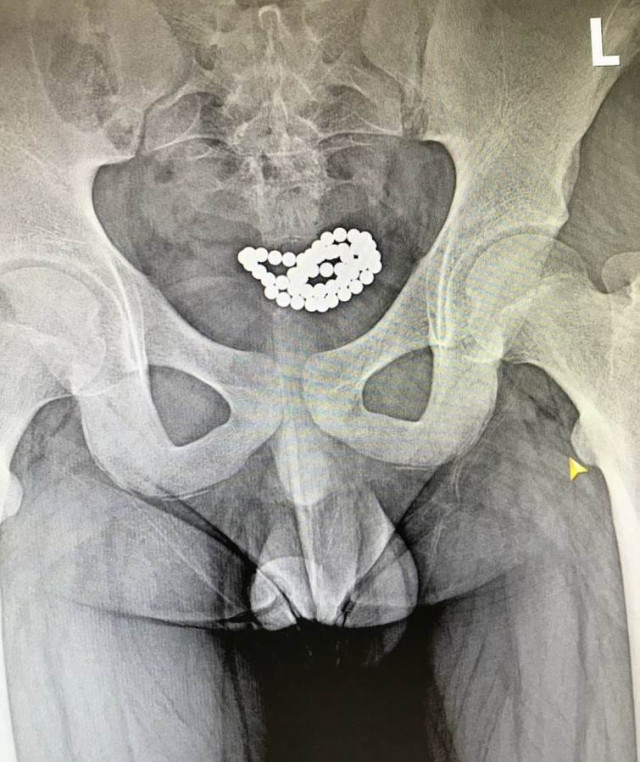

У Луцьку з сечових міхурів двох хлопчиків дістали понад 80 магнітних кульок

За останні три місяці в нашому закладі успішно було прооперовано два ідентичні випадки евакуації магнітних кульок з сечового міхура хлопчиків віком 10-15 років. В обох випадках було виконано цистотомію міні-лапаротомним доступом з подальшим вилученням 62 та 24 магнітних кульок.

Післяопераційний період у цих пацієнтів пройшов без ускладнень, і вони були виписані додому у задовільному стані», – йдеться у дописі.